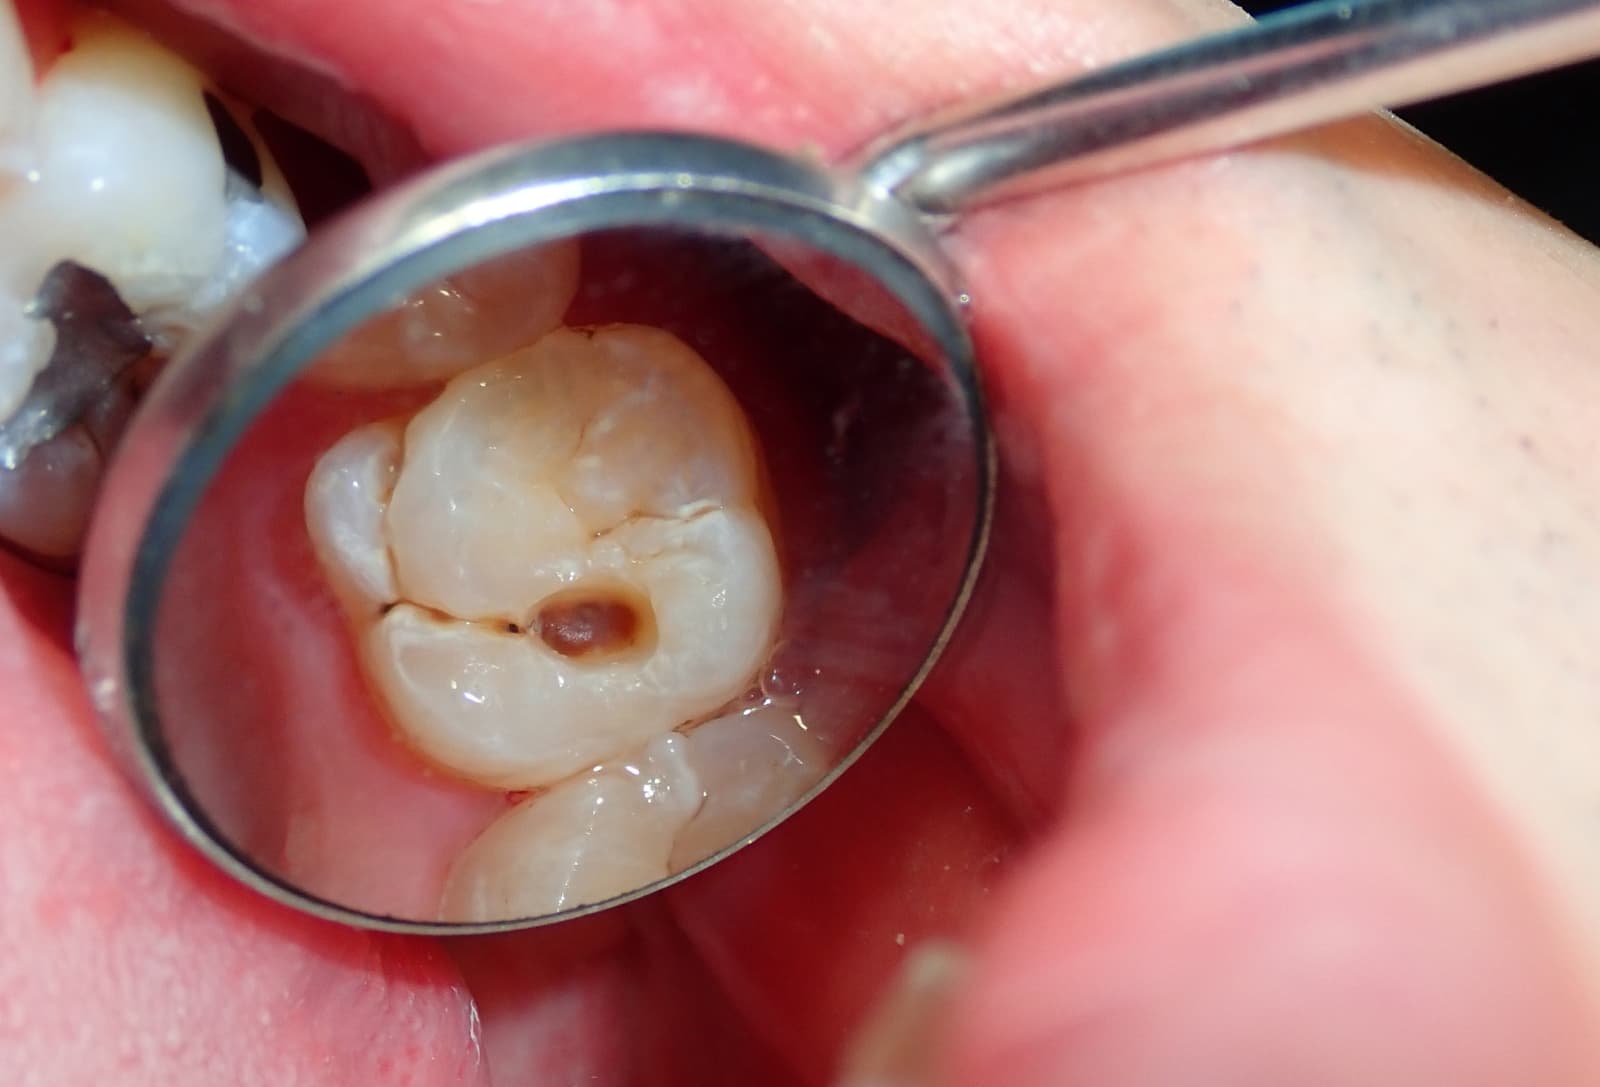

Cavities and tooth decay are among the most common oral health problems worldwide. They occur when the hard surface of your teeth, called enamel, is damaged by acids produced by bacteria. Over time, these acids can create tiny holes (cavities) that grow larger and deeper if left untreated.

Tooth decay can affect anyone, but the good news is it’s both preventable and treatable when detected early.

In its early stages, tooth decay might not cause noticeable discomfort. But as the decay worsens, symptoms become more obvious. Watch out for:

If you experience any of these signs, schedule a dental check-up promptly. Early intervention can prevent the decay from spreading and save your tooth.